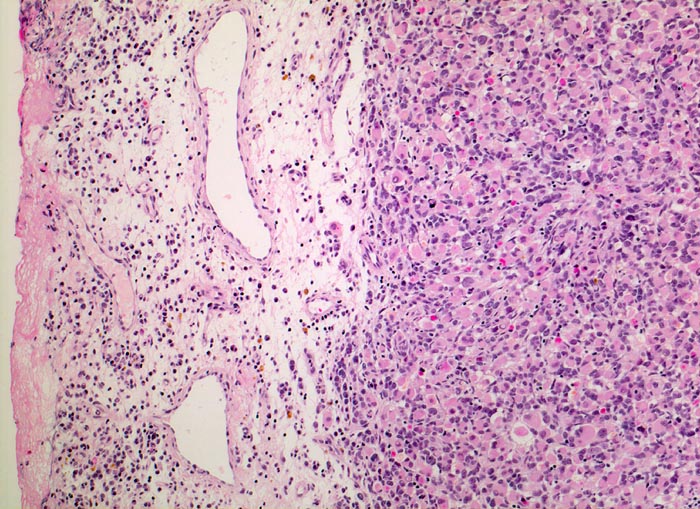

Das makroskopische Bild ist uncharakteristisch und variiert in Abhängigkeit von der Lokalisation. Fokale Nekrosen und zystische Degeneration sind häufig. Es werden verschiedene histologische Subtypen unterschieden, welche charakteristische molekulargenetische Aberrationen aufweisen und mit unterschiedlichen Prognosen assoziiert sind. Die beste Prognose haben botryoide und spindelzellige Rhabdomyosarkome gefolgt von embryonalen Rhabdomyosarkomen (intermediäre Prognose) und alveolären bzw. pleomorphen Rhabdomyosarkomen (schlechteste Prognose). Therapieantwort und Prognose hängen neben der Histologie auch von der Lokalisation ab. Embryonale Rhabdomyosarkome zeigen ein breites morphologisches Spektrum. Dieses reicht von wenig differenzierten Tumoren, die nur mittels Immunhistochemie und Elektronenmikroskopie diagnostizierbar sind zu gut differenzierten Tumoren, die fetaler Muskulatur ähneln. Oft findet sich eine Mischung von wenig differenzierten kleinen, runden und/oder spindeligen Zellen und eine variable Anzahl differenzierter Rhabdomyoblasten mit reichlich eosinophilem Zytoplasma. Die Rhabdomyoblasten können rund, spindelig, kaulquappenförmig oder spinnwebenförmig sein. Besser differenzierte Zellen enthalten reichlich Zytoplasma mit Querstreifung, welche allerdings teilweise nur elektronenmikroskopisch nachweisbar ist.

• Konjunktivalschleimhautfragment. Fibrinauflagerungen anstelle der langstreckig abgeschilferten konjunktivalen Zylinderepithelbedeckung (unten).

• Chronisches lymphoplasmazelluläres Entzündungsinfiltrat im subepithelialen Stroma mit unscharfer Begrenzung zu einem zellreichen soliden Tumor.

• Dieser besteht aus mesenchymalen Zellen mit unterschiedlicher Ausdifferenzierung.

• Die am wenigsten ausdifferenzierten Zellen zeigen wenig amphophiles Zytoplasma und ovale Kerne.

• Dominierend sind in diesem Tumor teils mehrkernige Rhabdomyoblasten mit reichlich eosinophilem Zytoplasma und exzentrischem Zellkern. Die Querstreifung des Zytoplasmas ist in der HE Färbung nur andeutungsweise erkennbar.

• "Spinnwebenzellen" mit peripheren Zytoplasmavakuolen.